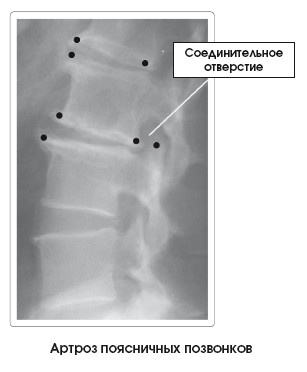

Иллюстрация к книге — Диагностика и лечение позвоночника. Уникальная система доктора А. М. Уриа [i_271.jpg]

Костные деформации (), называемые остеофитами, шпорами или пиками костей, характеризуют данное заболевание. Они бывают выраженными в той или иной степени в зависимости от уровня прогрессирования артроза. В зависимости от локализации процесса, размера и потери объема диска могут раздражаться и повреждаться структуры мягких тканей, такие как нервы, проходящие через соединительные отверстия, или межпозвоночные диски.

Для оценки состояния пациента применяют методы функциональной диагностики (рентген), объективного и субъективного обследования.